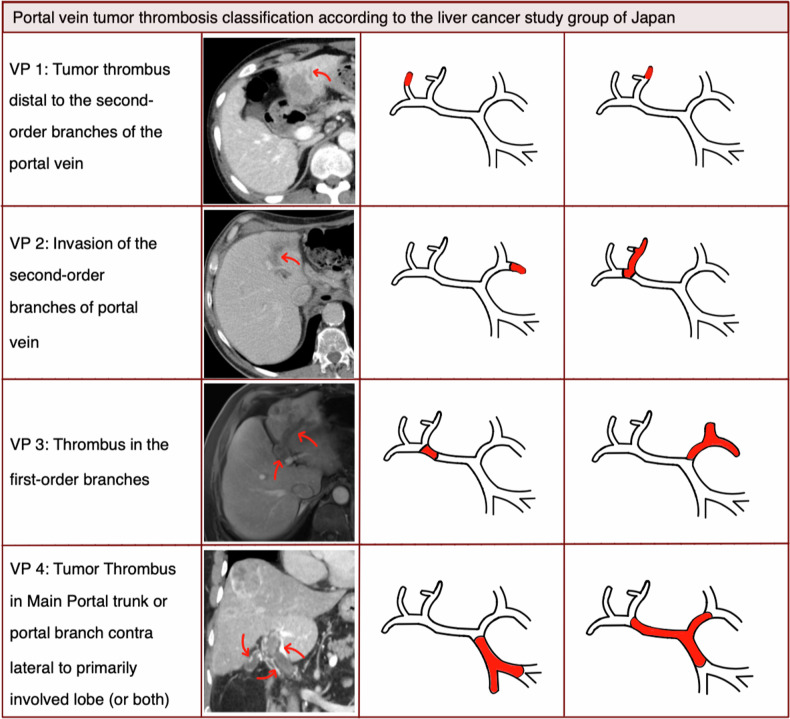

Methods: From January 2010 to January 2022, 56 patients (median age 67.5 years) with HCC and PVTT underwent 64 procedures. PVTT was further classified according to the Japan liver cancer study group into VP1-VP4. Tumor response was evaluated by cross-sectional imaging 6 weeks after CT-guided HDR brachytherapy and every 3 months thereafter. Local tumor control (LTC), progression-free survival (PFS), and overall survival (OS) were assessed using Kaplan-Meier curves. The severity of procedure-related complications was classified according to the Society of Interventional Radiology guidelines.

Results: Patients were available for imaging evaluation for a median follow-up of 14.0 months. The median diameter of the largest lesion was 56 mm. Estimated median PFS, LTC, and OS were 7.0 (95% CI 5.0-13.0), 14.0 (95% CI 7.0-21.0), and 20.0 (95% CI 13.0-26.0) months respectively. Actuarial 1-, 2-, and 3-year OS rates were 66%, 41%, and 27%, respectively. Subclassified for VP1, VP2, VP3, and VP4 estimated OS was 38.0 (95% CI 9.0-Not-a-number), 21.5 (95% CI 15.0-25.0), 15.0 (95% CI 7.0-33.0), and 13.0 (95% CI 6.0-34.0) months, respectively. Considering the 64 procedures, we recorded no complications for 49 (76.6%), mild-to-moderate complications for 12 (18.8%), and major complications for 3 (4.7%).